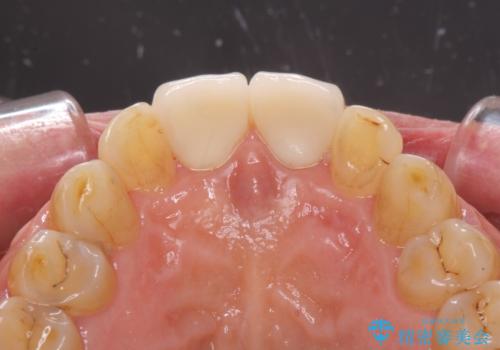

前歯の隙間をオールセラミッククラウンで自然に

折角なのできれいに仕上げたいとのことで、オーダーメイドタイプのクラウンを選択されました。色調を周りのご自身の歯と合わせることができるため、自然な仕上がりをご希望の方におすすめです。